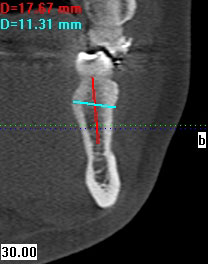

Im folgendem sehen Sie die Darstellung eines Teils des menschlichen Schädels mit Lokalisation des Nervkanales.

Sagittalansicht |

Coronalansicht |